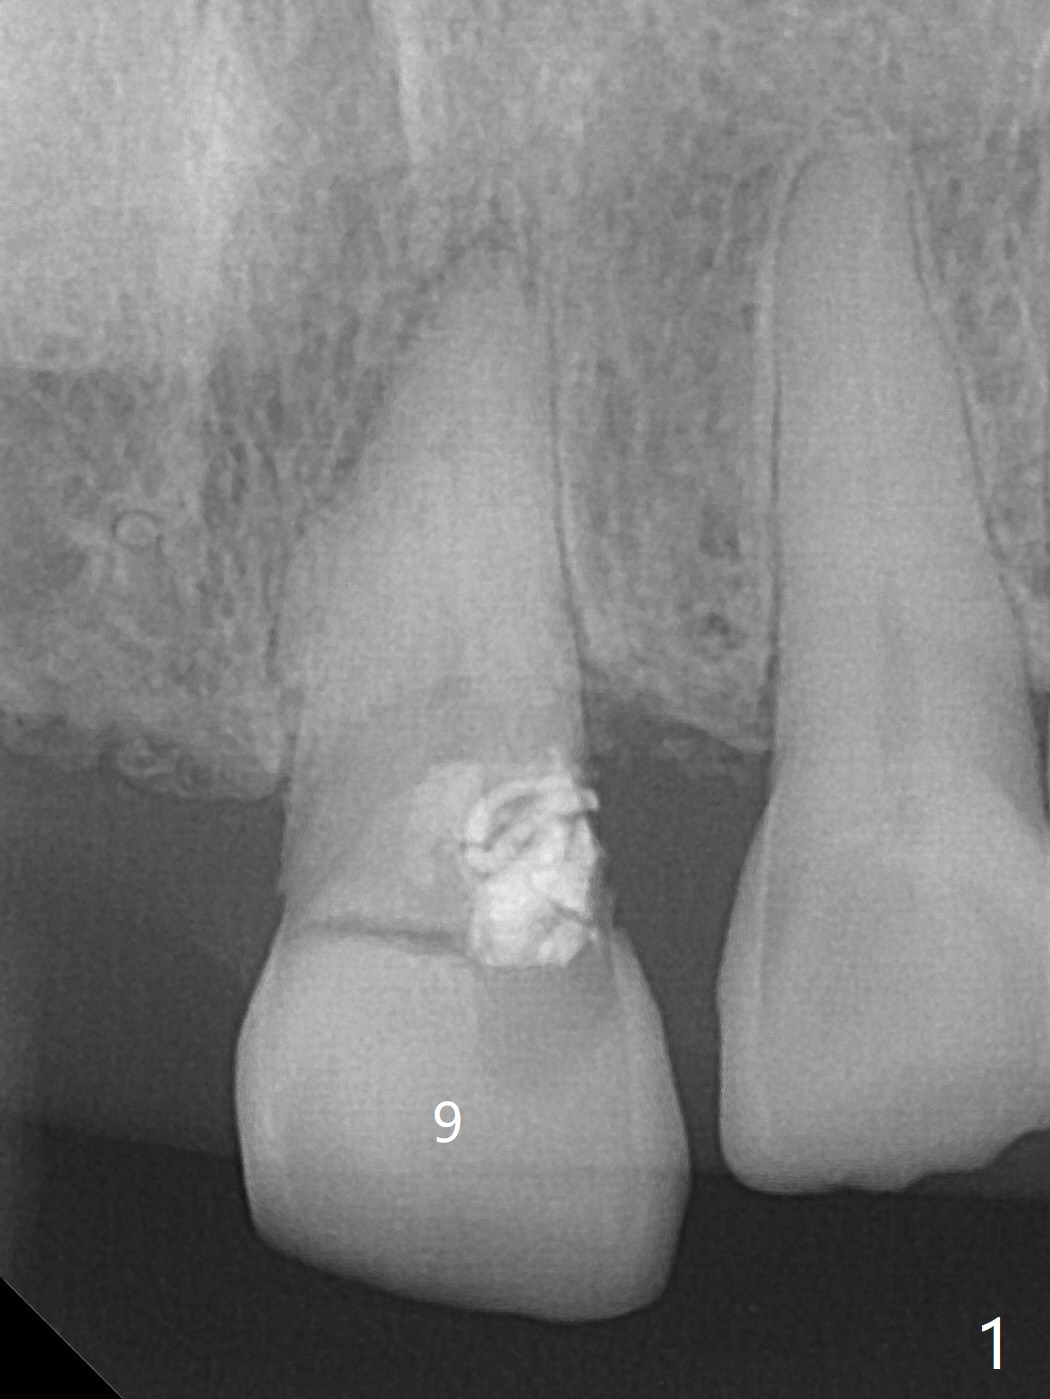

A 63-year-old woman with coronary artery disease and hypertension (taking 100 mg Aspirin daily with bleeding tendency) presents to office with subgingival fracture of the tooth #9 (Fig.1). After packing sticky bone into the extraction socket with a condenser (Fig.2), two pieces of PRF membranes are placed, followed by loose suturing with 4/0 Chromic gut suture (Fig.3). In fact the paper-thin buccal plate becomes bulging post bone graft condensation (*).